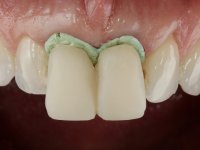

O tratamento iniciou-se com a confeção de moldeiras transparentes em silicone para aplicação de peróxido de carbamida a 16%. Os espaçadores colocados na superfície vestibular foram cuidadosamente preparados em resina nos modelos de gesso. O tratamento foi feito aplicando o produto 2 horas por dia durante 8 dias. Após o branqueamento esperamos 4 semanas e iniciamos o tratamento prostodôntico. Foi realizada uma pré-impressão em silicone para confeção de uma ponte provisória com resina composta de polimerização dual. Em seguida iniciamos a remoção das coroas. Foi feito um corte vertical na zona média da coroa até encontrar a superfície do espigão falso coto fundido. No bordo incisal também foi realizado o mesmo corte. Em seguida com um luxador fino foi feita a separação das partes distais das coroas. Para a remoção das partes mesiais foi feito um corte na linha média abrangendo ambas as coroas. No final da remoção atraumática das coroas antigas os cotos foram re -preparados. Na re-preparação dos cotos a linha de acabamento foi colocada a nível intra-sulcular. Na mesma consulta foi feita a impressão definitiva. O afastamento gengival foi realizado com a técnica da pasta de caolino comprimida pela ponte provisória.  A impressão foi feita pela técnica de dupla mistura com dupla viscosidade com silicone de presa rápida. No laboratório foram confecionadas 2 coroas com infraestrutura em Zr sendo revestidas a cerâmica. No sentido de evitar aparência de coroas “muito altas” foi aumentado ligeiramente o diâmetro mesio-distal sobrepondo-se ligeiramente aos dentes adjacentes. A ponte provisória foi removida os cotos foram polidos e as coroas foram colocadas para verificação final. Confirmado o seu ajuste e aprovadas pela paciente foram cimentadas definitivamente com cimento de ionómero de vidro reforçado com resina.